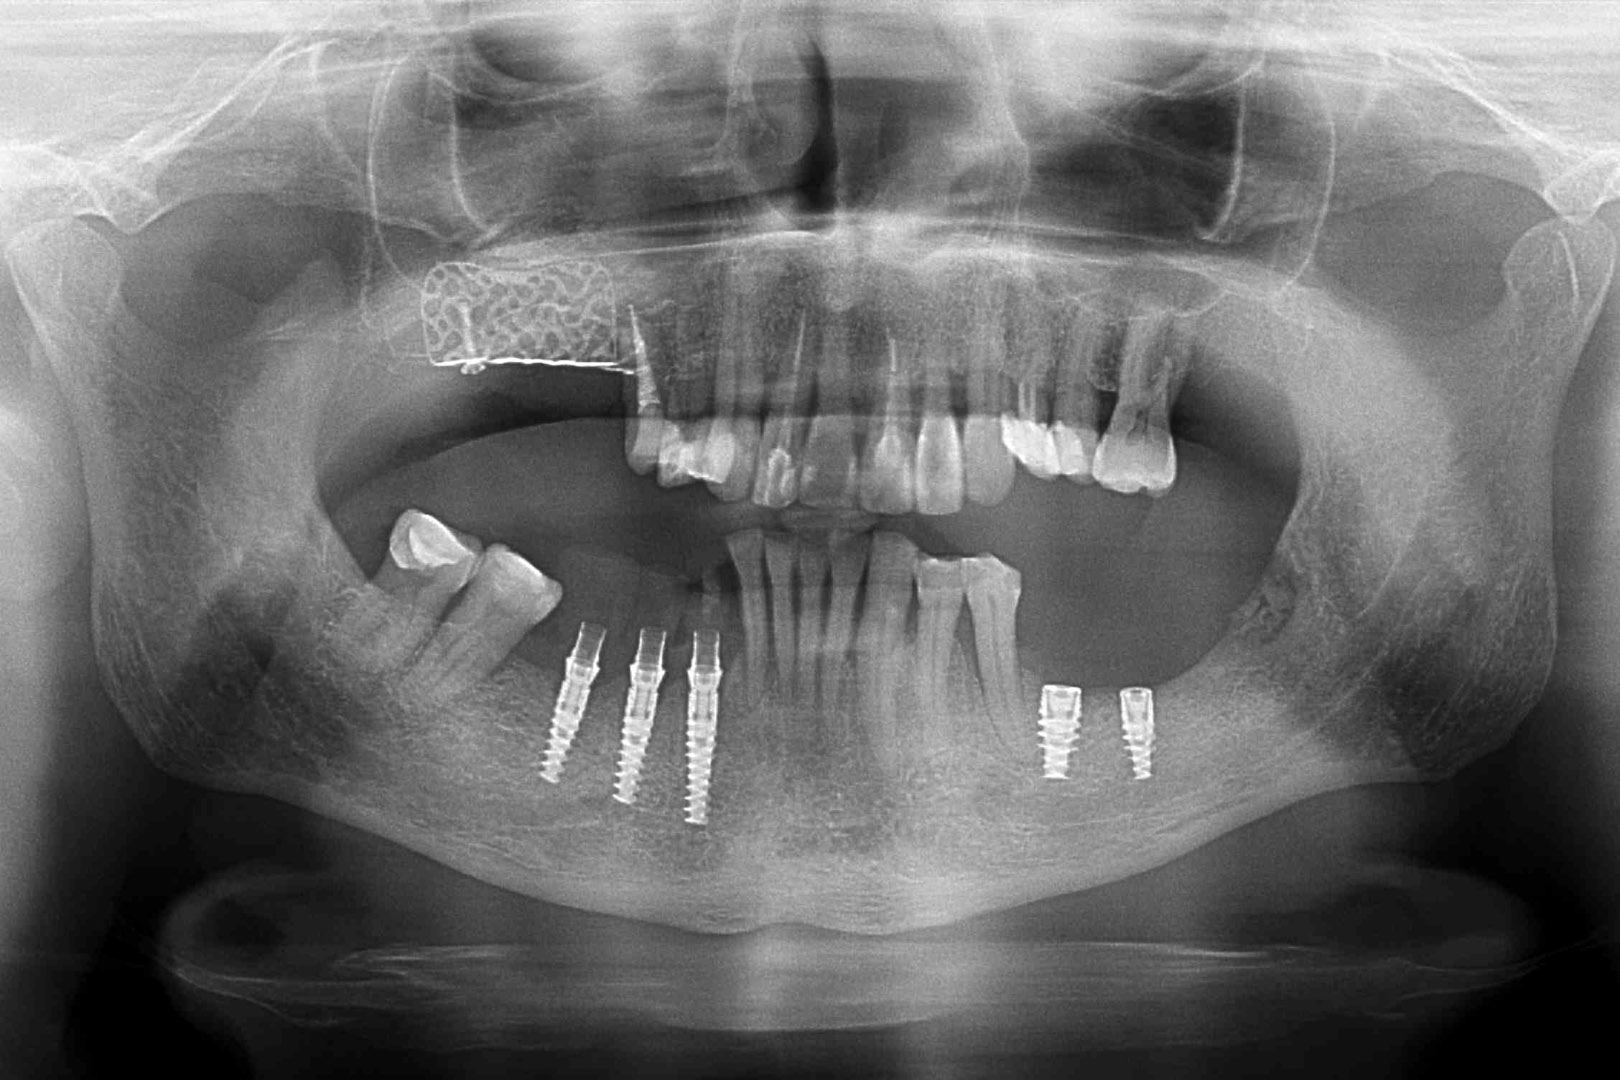

Przed podjęciem leczenia należy określić stopień zaniku kości szczęk oraz żuchwy. W tym celu przeprowadza się badanie kliniczne oraz odpowiednią diagnostykę obrazową pacjenta. Uwzględnia ona zdjęcie panoramiczne OPG jako podstawę dwuwymiarowego obrazowania podłoża kostnego oraz możliwe jest badanie tomograficzne CT lub bardziej precyzyjna tomografia stożkowa CBCT. Opcjonalnie wykorzystywana diagnostycznie tomografia pozwala na bardziej wnikliwą ocenę stopnia zaniku kości w trójwymiarowym, przestrzennym obrazie.

Procedury te są stosowane w sytuacji niedostatecznej ilości kości, skutkującej odsłonięciem gwintu, podczas gdy wszczepiamy implanty stomatologiczne lub też jako zabiegi poprzedzające ich wprowadzenie.​

Zabiegiem, który rozwiązuje ten problem, jest podniesienie dna zatoki szczękowej, czyli odbudowa kostna w okolicy zębów trzonowych. Ubytek kości uzupełniany jest materiałem kościotwórczym, który układany jest pod błoną wyścielającą zatokę szczękową, zwaną membraną Schneidera. Zmniejszając objętość zatoki szczękowej, tworzy się tym samym stabilną strukturę kostną, umożliwiającą zabieg implantacji wszczepów śródkostnych.

Metoda rekonstrukcji kostnej w oparciu o indywidualnie drukowane siatki z tytanu dla implantacji wszczepów śródkostnych stosowana jest najczęściej jako dwuetapowa. W pierwszym etapie odbudowywana jest kość, natomiast implanty wszczepiane są po okresie 4–6 miesięcy. Na wgojenie implantów oczekujemy od 4 do 6 miesięcy w zależności od miejsca ich lokalizacji. Siatka tytanowa po spełnieniu swojej funkcji rusztowania dla odbudowującej się kości jest następnie usuwana w dniu wszczepienia implantu. Jeżeli kość spełnia odpowiednie warunki, istnieje możliwość zastosowania modyfikacji siatki tytanowej, która umożliwia jednoczesne wprowadzenie implantów wraz z odbudową kostną. Wariant ten skraca czas od pierwszego zabiegu do wykonania gotowych koron protetycznych na wprowadzonych implantach.

WYBRANE PRZYPADKI REKONSTRUKCJI 3D PRZY UŻYCIU SIATEK TYTANOWYCH REOSS